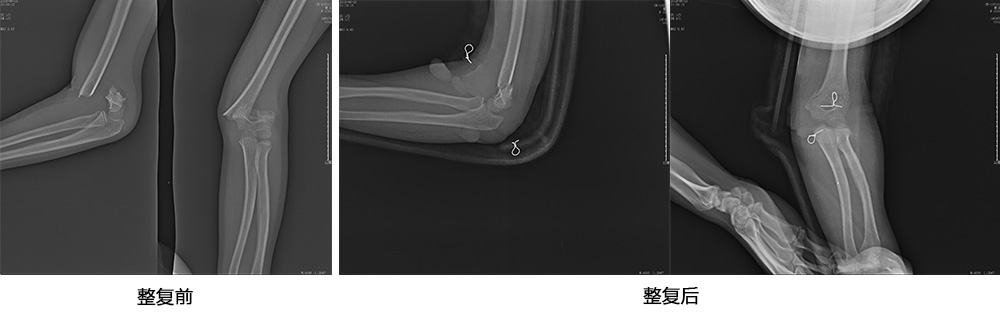

傳統(tǒng)手法整復(fù)病例影像

CR94676